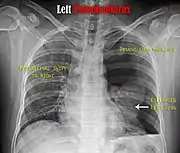

Chest X-ray

A plain chest radiograph, ideally with the X-ray beams being projected from the back (posteroanterior, or "PA"), and during maximal inspiration (holding one's breath), is the most appropriate first investigation.[30] It is not believed that routinely taking images during expiration would confer any benefit.[31] Still, they may be useful in the detection of a pneumothorax when clinical suspicion is high but yet an inspiratory radiograph appears normal.[32] Also, if the PA X-ray does not show a pneumothorax but there is a strong suspicion of one, lateral X-rays (with beams projecting from the side) may be performed, but this is not routine practice.[15][19]

It is not unusual for the mediastinum (the structure between the lungs that contains the heart, great blood vessels, and large airways) to be shifted away from the affected lung due to the pressure differences. This is not equivalent to a tension pneumothorax, which is determined mainly by the constellation of symptoms, hypoxia, and shock.[13]

The size of the pneumothorax (i.e. the volume of air in the pleural space) can be determined with a reasonable degree of accuracy by measuring the distance between the chest wall and the lung. This is relevant to treatment, as smaller pneumothoraces may be managed differently. An air rim of 2 cm means that the pneumothorax occupies about 50% of the hemithorax.[15] British professional guidelines have traditionally stated that the measurement should be performed at the level of the hilum (where blood vessels and airways enter the lung) with 2 cm as the cutoff,[15] while American guidelines state that the measurement should be done at the apex (top) of the lung with 3 cm differentiating between a "small" and a "large" pneumothorax.[33] The latter method may overestimate the size of a pneumothorax if it is located mainly at the apex, which is a common occurrence.[15] The various methods correlate poorly but are the best easily available ways of estimating pneumothorax size.[15][19] CT scanning (see below) can provide a more accurate determination of the size of the pneumothorax, but its routine use in this setting is not recommended.[33]

Not all pneumothoraces are uniform; some only form a pocket of air in a particular place in the chest.[15] Small amounts of fluid may be noted on the chest X-ray (hydropneumothorax); this may be blood (hemopneumothorax).[13] In some cases, the only significant abnormality may be the "deep sulcus sign", in which the normally small space between the chest wall and the diaphragm appears enlarged due to the abnormal presence of fluid.[16]